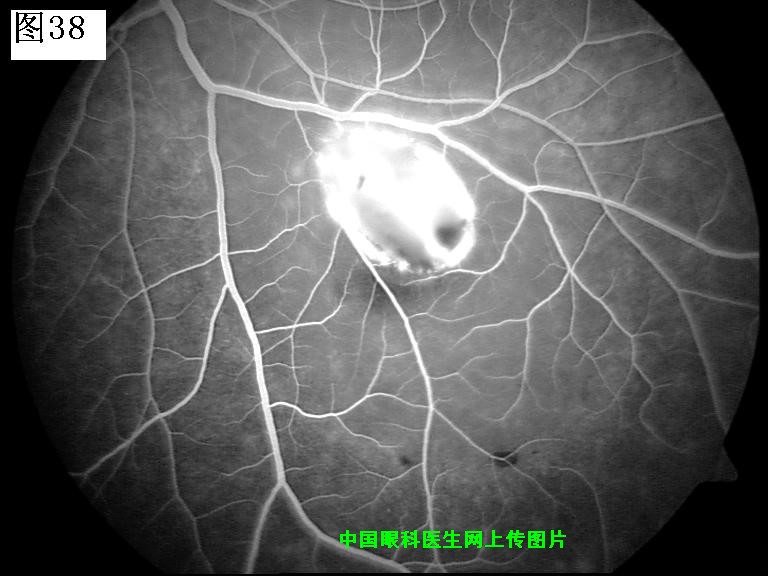

37 38 39 40